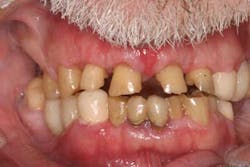

Case study A 58-year-old male with a noncontributory medical history presented to a private practice for a complete rehabilitation of his dentition due to years of bruxism and parafunction. (Fig. 1) After surgical and restorative consultations, a treatment plan was fabricated. The treatment plan included restoring his lost vertical dimension, restoring his natural dentition with porcelain-fused-to-metal full-coverage crowns, and replacing his lost posterior teeth with dental implants. After his vertical dimension was restored with an acrylic bite plate to a position harmonious with TMJ function, crown-lengthening surgery was performed. (Fig. 2)Fig. 2 Six weeks after, the teeth were temporized to develop soft tissue margins/interdental papillae. (Figs. 3 and 3a) The patient was kept in temporaries for three months, during which time an implant was placed in site No. 19. Both the natural dentition and the implant were completed at the same time, three months after implant placement. (Fig. 4) Because of the patient’s occlusal issues, the implant was screw-retained, and the patient was given a maxillary night guard. Three weeks after insertion, the patient presented with a loose abutment screw. The dentist tightened the screw and sent the patient home. This cycle was repeated two more times until the patient presented again with a loose crown, but this time, a fracture implant screw. The dentist attempted to remove the screw with a Cavitron and drilling the implant screw out to release preload, but to no avail. The case was then referred to my office for implant removal.